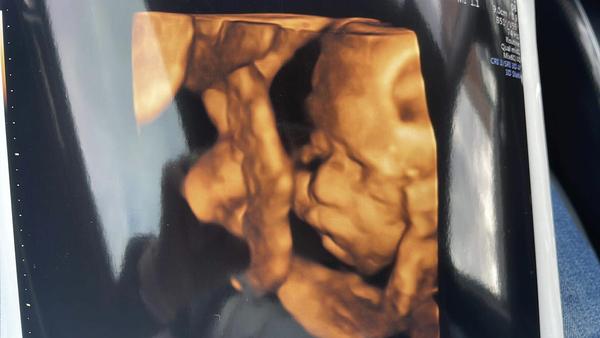

@luuc5 ahoooj, jde to.. 🙃 v úterý jsem byla na UTZ (11tt) a vypadá to na kluka. Příští týden jdu na screening, tak uvidíme jestli se potvrdí. Spíš jo. Jeden záběr na UTZ mluvil úplně jasně, nechápu jak ten čtyřcentimetrový tvoreček může mít už v 11 TT takovou výbavu 😁 včera jsem jenom z legrace před máti nahodila téma dalšího vnoučete (toto bude páté). Řekla: už se na to prosímtě vykašlete 😄 no bude to zajímavé 🤔